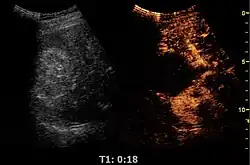

Contrast-enhanced renal ultrasonograph, showing a renal cell carcinoma successfully treated with thermal ablation, as no contrast enhancement is seen[1]

Unspecific cortical lesion on CT is confirmed cystic and benign with contrast-enhanced renal ultrasonography using image fusion.[1]